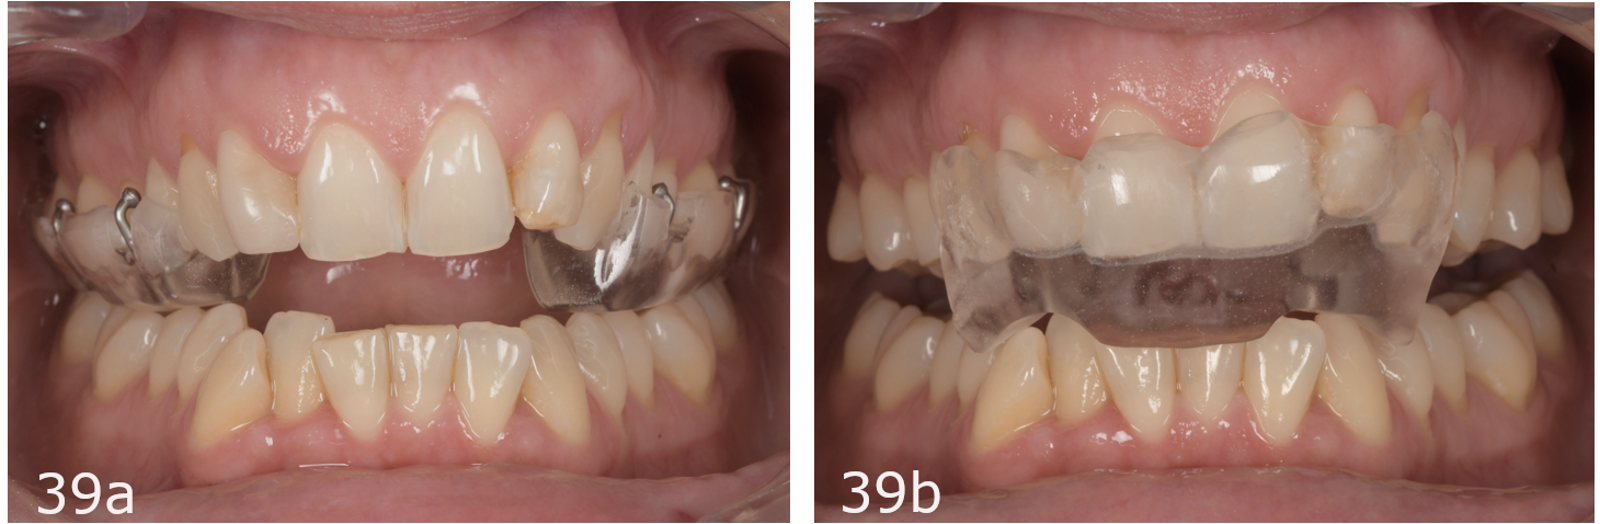

In the case of orthopaedically unstable patients, a stable arc of closure must be achieved before starting any orthodontic treatment. Stabilisation is achieved with an occlusal splint, and once stabilised, this position must be maintained until the end of treatment to attain orthopaedic stability. Splints must be worn 24 hours a day, seven days a week. We use a two-piece splint, and both parts are constructed at the same vertical dimension of occlusion. The anterior splint covers the six anterior teeth (incisors and canines), and the posterior splint is united by a palatal bridge and covers the premolars and molars.

The anterior splint opens the bite and avoids posterior contacts, diminishing the muscular activity and restoring symmetrical function. By increasing the vertical dimension, we obtain relaxation of the elevator and depressor muscles. Patients wear it during sleep, ideally for at least eight hours. This splint allows repositioning of the condyles upwards and forwards and harmonising of the neuromuscular system by eliminating clenching and parafunction. During the day, patients wear the posterior splint, allowing seating of the condyles, stabilisation of dental contacts and recovery of the true arc of closure. The two-piece splint is much better accepted by patients since it produces no aesthetic problems and thus encourages greater compliance.49

The stabilisation phase was carried out with a full-time two-piece splint. The patient wore the posterior part during the day in order to achieve stable contacts with the antagonist teeth (Fig. 11). The anterior part, worn during the night, helped to eliminate clenching and parafunction (Fig. 12). Regular adjustments were made until we achieved stable occlusal contacts, allowing the condyles to seat, first recovering and then maintaining the arc of closure during the process.

Considering the joint instability, our initial treatment began with a splint (Fig. 39). After four months of treatment with the splint, the condylar position was stable, the condyles rotated and the patient was completely asymptomatic. However, her occlusion had changed to more of a Class II malocclusion, and she had developed a larger open bite owing to the mandibular clockwise rotation (Fig. 40).